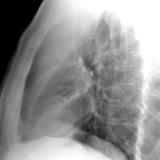

LUL Collapse Case 1 Lateral

Date: 02/19/2004

Views: 3319